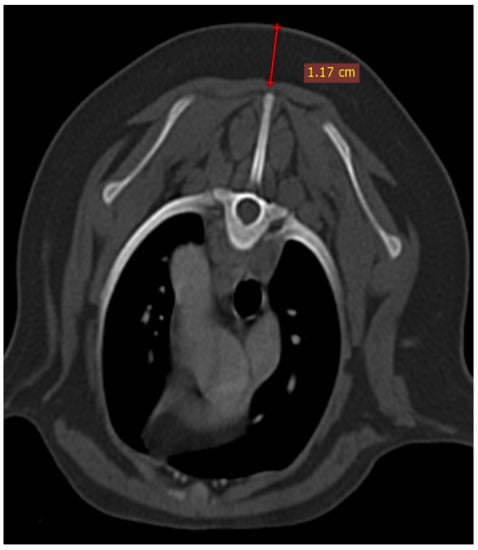

The thymus was evaluated in the first step to determine whether it was visible or not. Non-visible thymus was that with complete degeneration seen with fat attenuation and not distinguishable from mediastinal fat. After that, a grading system for thymic tissue appearance was used based on its predominant component (grade 0: totally fatty replacement of the thymus (non-visible) and could not differentiate from mediastinal fat; grade 1: more than 50% fatty replacement of the thymus; grade 2: more than 50% soft tissue component in the thymus; grade 3: totally soft tissue component in the thymus. After grading the thymus, the attenuation (CT number) of thymic tissue in plain and contrast-enhanced images was measured. For this purpose, a round-shaped region of interest (ROI) with a surface equal to 75 mm2 was considered in the widest part of the organ for large thymus (Figure 1) and a smaller ROI for small thymus. Then pre- and post-contrast Hounsfield Units (HU) were compared for each patient individually and also between groups for evaluating the pattern of attenuation alteration and enhancement alteration.

3.1. Visibility

In the present study, the thymus was visible in 104 out of 150 cases. The distinct lobes of the thymus were not distinguishable. The visible thymus was noted with a soft tissue component and homogenous appearance or a combination of soft tissue and fat component based on the degree of involution with heterogenous (mottled) appearance (Figure 4, Figure 5 and Figure 6). We accounted the thymic tissues with complete fat degeneration for non-visible thymus (Figure 7). The anatomical and topographical locations of the thymus are shown in Figure 4, Figure 5, Figure 6 and Figure 7. The thymus’ dorsal border begins at the ventral aspect of the vessels in the cranial mediastinum and ends at the dorsal aspect of the sternebra. In the dorsal and sagittal views, it was extended caudally up to the pericardial region and merged with the pericardium on the left side (Figure 2B). The visibility percentage in group 1 was 100%. The minimum and maximum ages in group 1 were three and six months, respectively. In groups 2 and 3, the thymus was visible in 86.7% of cases and it was not notable in 13.3% of cases. The minimum and maximum ages with visible thymus in group 2 were seven and 12 months, respectively. This group includes one 11-month-old and three 12-month-old cases with a non-visible thymus. In group 3, the youngest and oldest cases with a visible thymus were 1.5 and 2 years old. The patients with a non-visible thymus were two years old. In group 4 the visibility percentage was 53.3% and the thymus was not visible in 46.7% of patients. The youngest and oldest patients with visible thymus in group 4 were three- and six-year-old dogs. The visibility percentage of group 5 was 20% and the maximum age with visible thymus was nine years old (Table 1).

Figure 1. Illustration of density measurement of thymus in plain (right) and post-contrast (left) CT scan examination in a ROI equal to 75 mm2. These figures belong to a four-month mixed-breed male puppy. The grey dash lines show the grade3 rectangular-shaped midline-position thymus. S: scapula, TV: thoracic vertebra, R: rib, E: esophagus (which is dilated due to general anesthesia), T: trachea, CrVC: cranial vena cava, and asterisk: second sternebra.